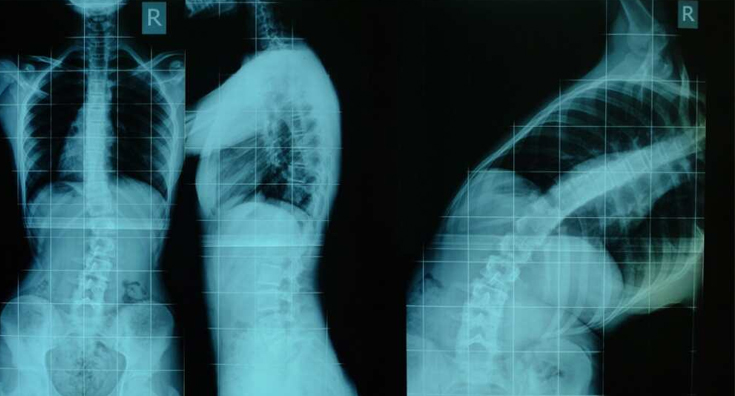

ΠΟΥ ΠΡΟΟΡΙΖΕΤΑΙ

Πρόκειται για ένα κηδεμόνα που προορίζεται μόνο για οσφυϊκές σκολιώσεις και αρκετά εύκαμπτες. Αυτό μπορεί να διαπιστωθεί με λήψη ακτινογραφίας σε μέγιστη πλάγια κάμψη (Bending Test).